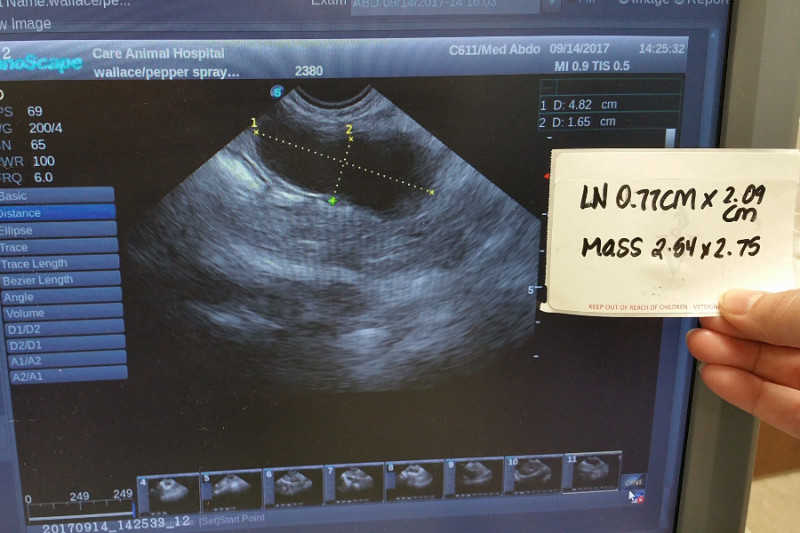

Not the best of news...My latest ultrasound shows my tumor has increased in size over the last 20 days. The note in the pic is from my original ultrasound @ Lakeshore Veterinary Specialists. This is my X ray from Lakeshore. You can see the growth that is causing my troubles. It's pushing on my colon and bladder, so it's a bit uncomfortable. Luckily I have spent many years grooming my Humans to notice and help me with such things. The meds I am taking seem to help greatly with my discomfort. Thank you all so much for your help in making them attainable. Love. Wallace...Ok, here We go...The information from my blood panel(s) is not good, in fact it's really bad. The growth in my belly that seems to be causing my intestinal problems is by all indications, malignant. That's right, cancer. My globulin/protien levels basically leave no doubt. The good Doctor estimated 3 to 6 months before I can no longer fight this. My loving  Humans are doing everything in their power to make my limited time as comfortable and enjoyable as possible. As you can well imagine, this does/will involve many fairly expensive medications/tests and follow up visits to the Doc . They are also currently  experiencing health problems and due to the fact that there will be absolutely no heath insurance for them  untill the beginning of the calender year, this has all become overwhelming financially. Any help at all will be greatly appreciated. We are also in the process of working on some small gifts for everyone for showing so much love and support. This is a pic of me turning away from my meds. I know they are helpful, but I don't have to like taking them. We will keep you all updated as much as possible. Love. Wallace...We got some bad news from my doctor recently. The results are currenly posted on Instagram, I'll post more info here tomorrow when I can. Thank You All so much for caring. Turns out I was a bit more than just "feeling under the weather". Doc gave me a maximum of 12 hours to live without emegency procedures....And nataurally it had to be late and on a weekend. As you can well imagine, that basically doubles any fees/costs.    Part2... I'm feline a bit naked without my belly fur, trying to rest comfortably...At the emrgency hospital, the good Doctor and staff #lakeshoreveterinaryspcialists were able successfully drain my bladder, externally with a needle without rupturing it. I had a large amount of fecesbacked up, so theygave me a stool softener. When the was finally inserted, there was concern. There was no evidence of the suspected crystal blockage. Once I was emptied the x rays showed an abnormal growth/mass in my abdomen that is putting pressure on colon and bladder, this is why I was unable to empty either. They suspect I also have a bladder infection due to the high white blood cell count in my urine sample.An xX-ray was taken of my lungs, they are clear. They also discovered evidence of heart diease and a heart murmur. We are waiting for culture results from the lab from samples taken last weekend at the hospital. This morning I was admitted to the great care of my primary Dr. #careanimalhospital for a 12 hour glucose scrren and blood panel testing.'m on 5 different medications now. Some of them seem to be fighting each other. Since everything affect everything else, we need to get all my different conditions and meds in synch. We will have a better understanding of  my health after this current round of tets. I will post new info as it is recieved. Thank you all for your support, donations, well wishes and encouragement. I would not be here right now without it. The adventure continues....